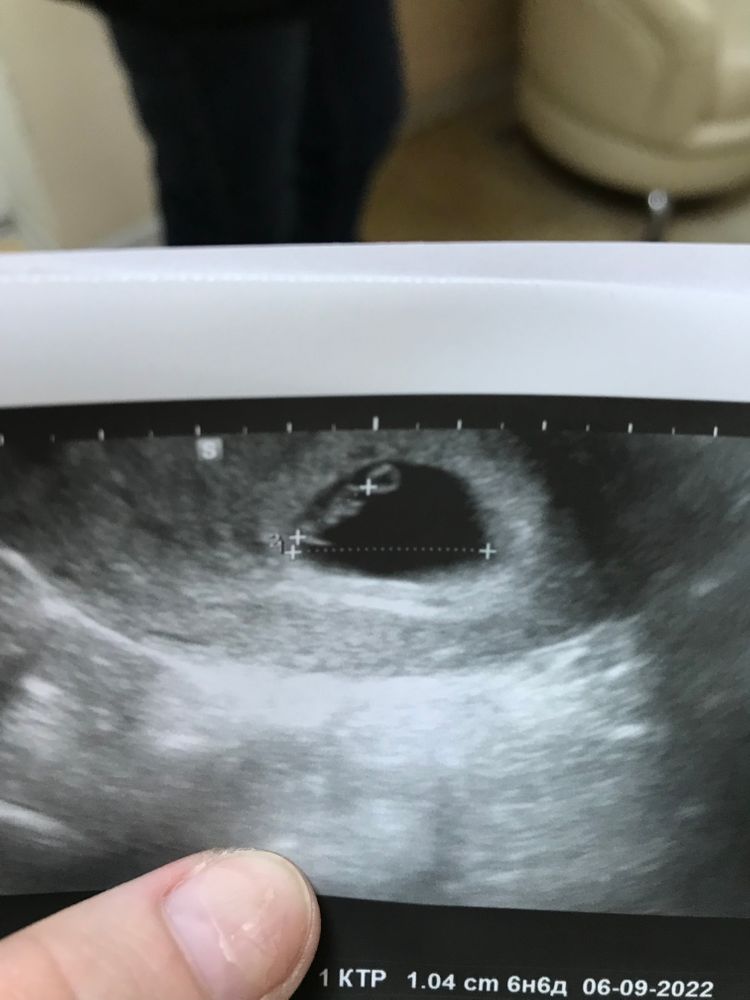

Первое УЗИ

Первое узи с сб+ Про погрешности в узи..